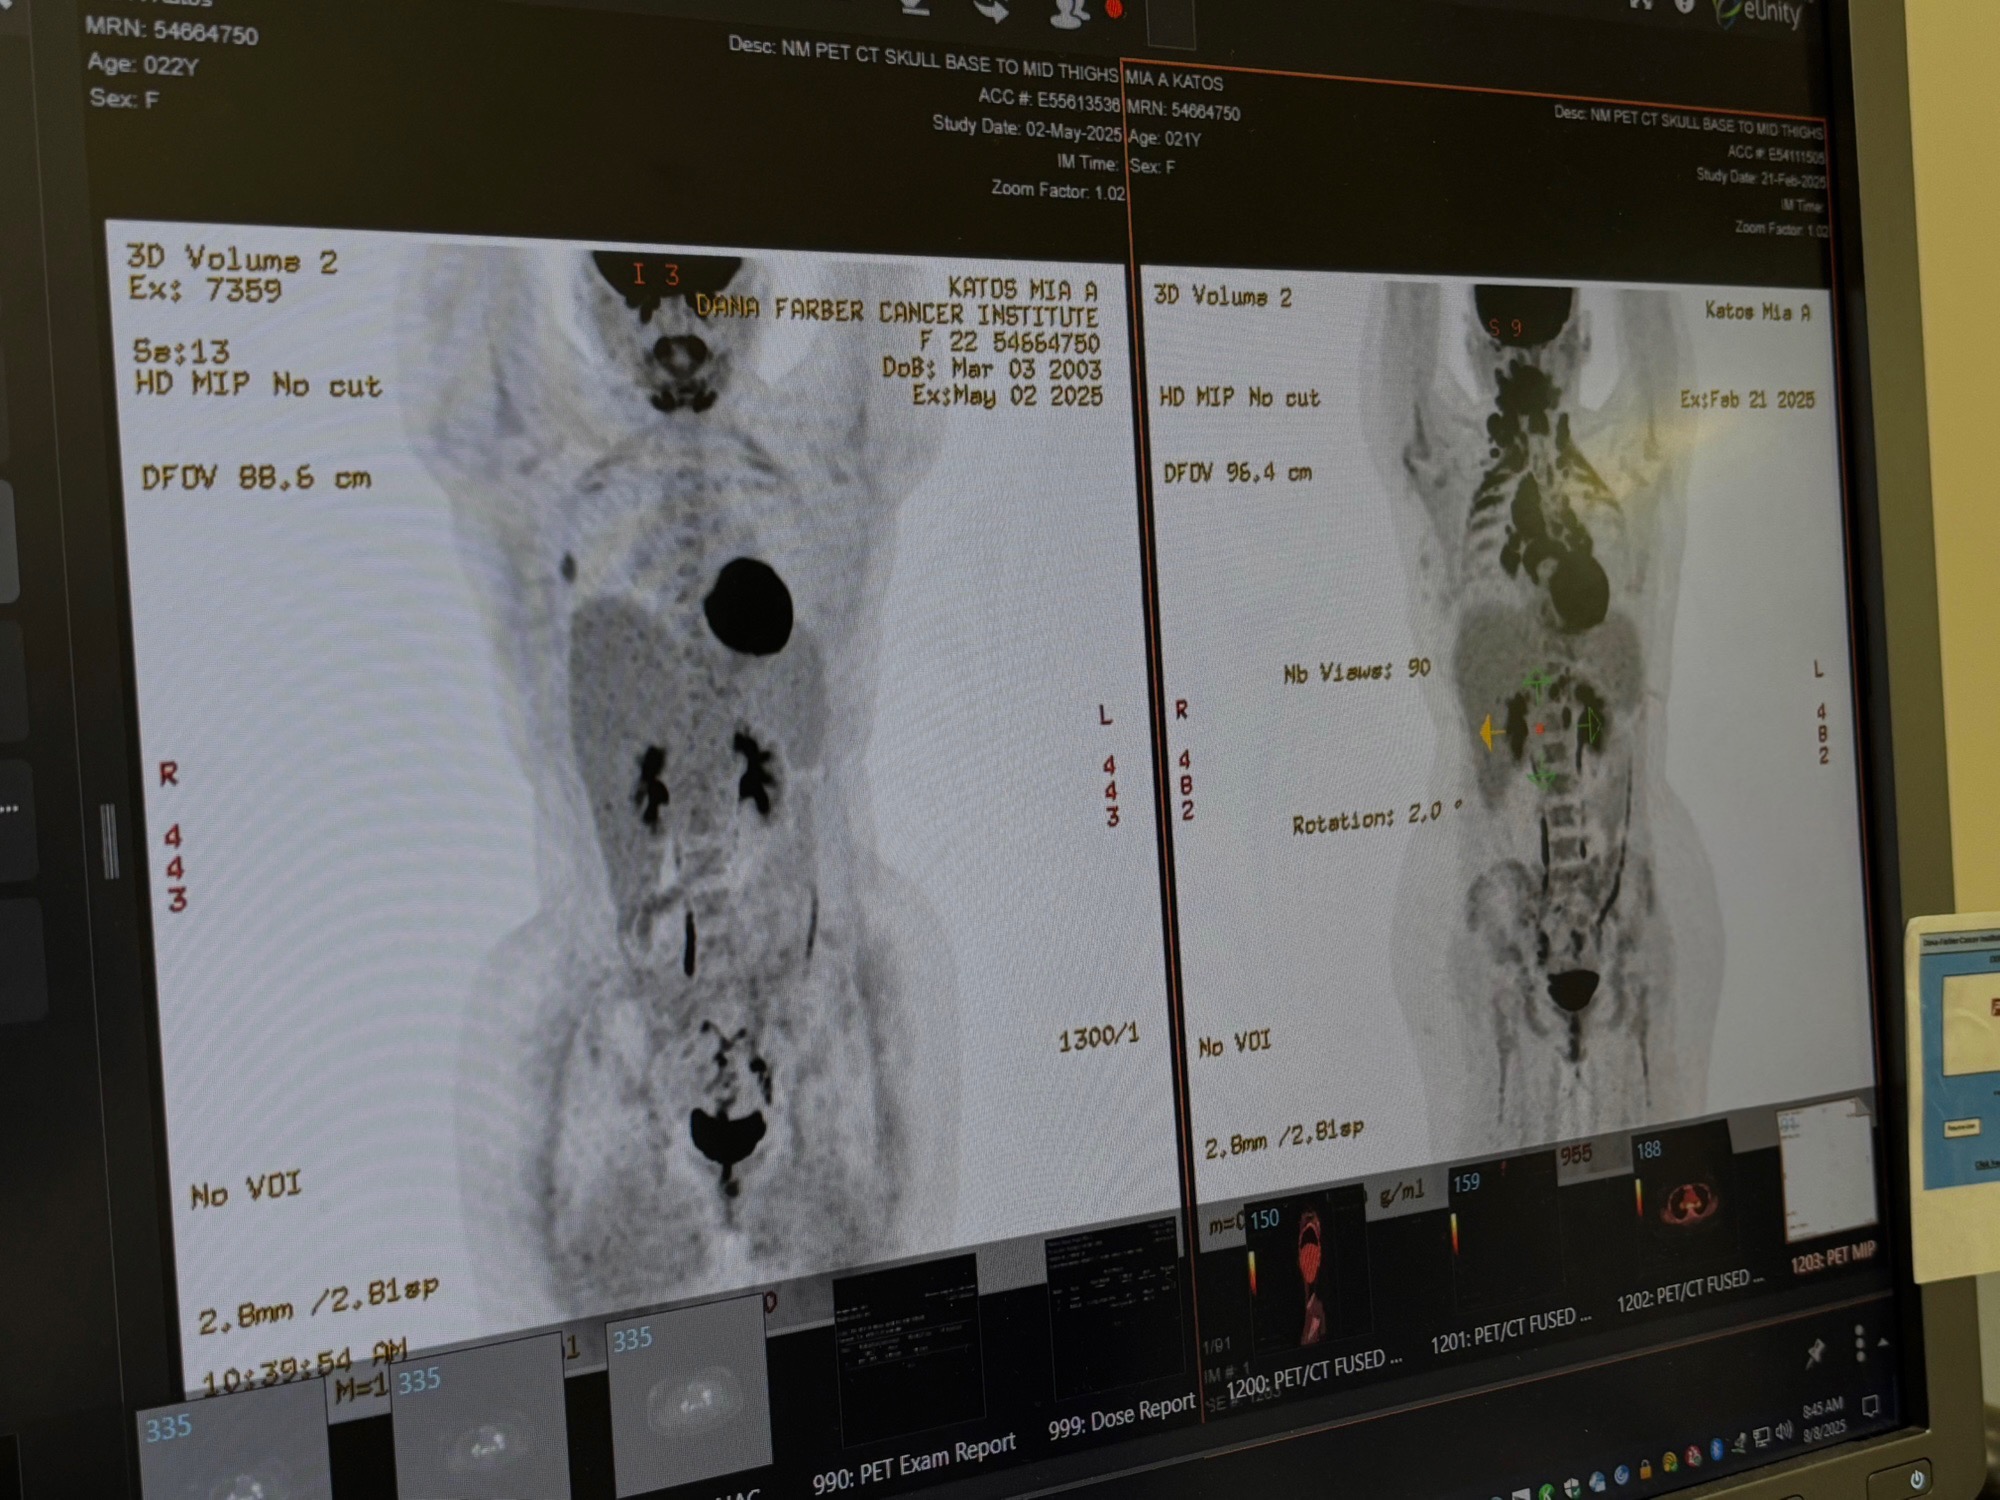

This past year things got even harder because I was diagnosed with stage four lymphoma cancer throughout my body and recently my chemo caused ketoacidosis that put me in the ICU for five days. I had hours left before I was about to slip into a coma and I am now left with an life long adrenal insufficiency, which means my body can no longer produce enough stress hormones to survive on its own. I have to wear a medical alert bracelet for life, mobility aids, and take multiple additional medications every day just to function.